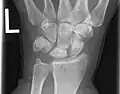

Kienböck's disease

Kienböck's disease is a disorder of the wrist. It is named for Dr. Robert Kienböck, a radiologist in Vienna, Austria who described osteomalacia of the lunate in 1910.[1]

It is breakdown of the lunate bone, a carpal bone in the wrist that articulates with the radius in the forearm. Specifically, Kienböck's disease is another name for avascular necrosis[2] (death and fracture of bone tissue due to interruption of blood supply) with fragmentation and collapse of the lunate. This has classically been attributed to arterial disruption, but may also occur after events that produce venous congestion with elevated interosseous pressure.